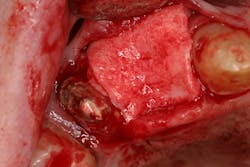

- Antiseptic mouthrinse. StellaLife has been shown to assist in tissue healing and prevent possible infections in areas of open wounds in multiple case series (figures 3–9).1